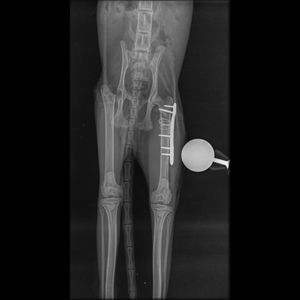

Há algum tempo, lançamos uma vaquinha para ajudar nossa querida gatinha Mikasa a passar por uma cirurgia ortopédica no fêmur. Graças à generosidade e ao apoio de cada um de vocês, conseguimos alcançar esse objetivo com sucesso! Mikasa está se recuperando bem da cirurgia e já está começando a explorar novamente sua casa com sua curiosidade característica.

No entanto, como sabem, os cuidados com um animalzinho não param após a cirurgia, ela terá 90 dias de cuidados pós cirúrgicos.

Ela irá precisar fazer uma serie de exames para acompanhamento da evolução da cirurgia e também medicamentos.